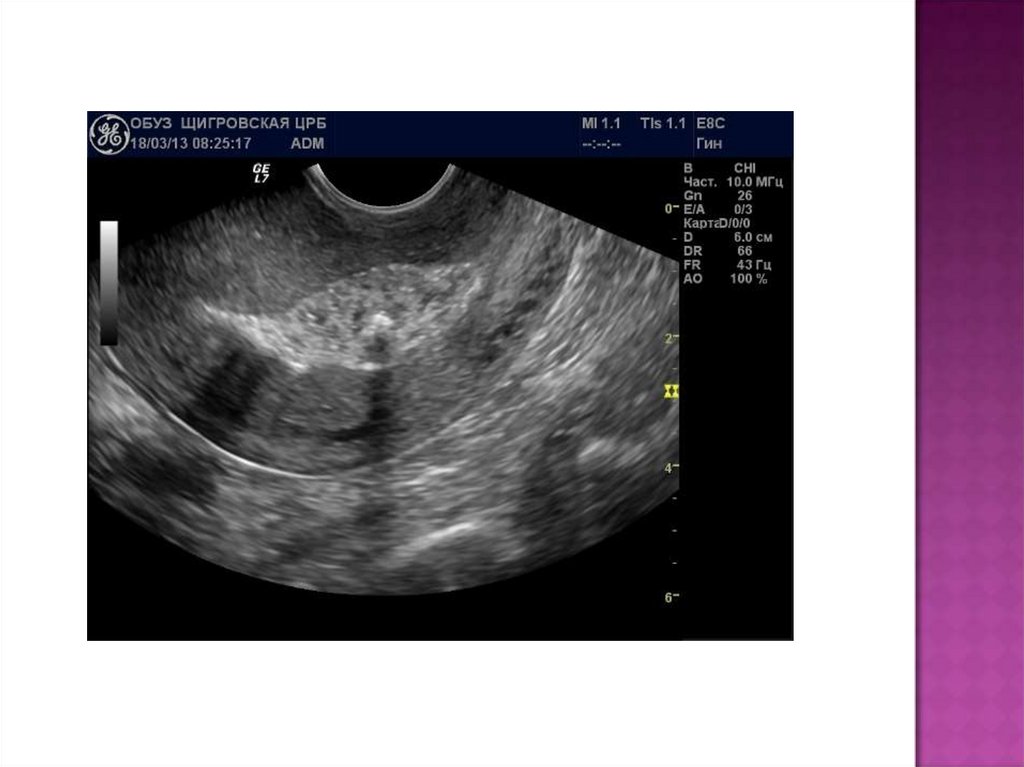

УЗИ:

УЗИ позволяет заподозрить данное заболевание по

сочетанию признаков:

·субинволюция матки;

·расширенная полость матки со множеством точечных

эхопозитивных включений (пузырьки газа);

·выраженный гипоэхогенный контур полости матки

(инфильтрация).

С помощью УЗИ можно обнаружить фрагменты последа

(эхопозитивные наложения на стенках матки).